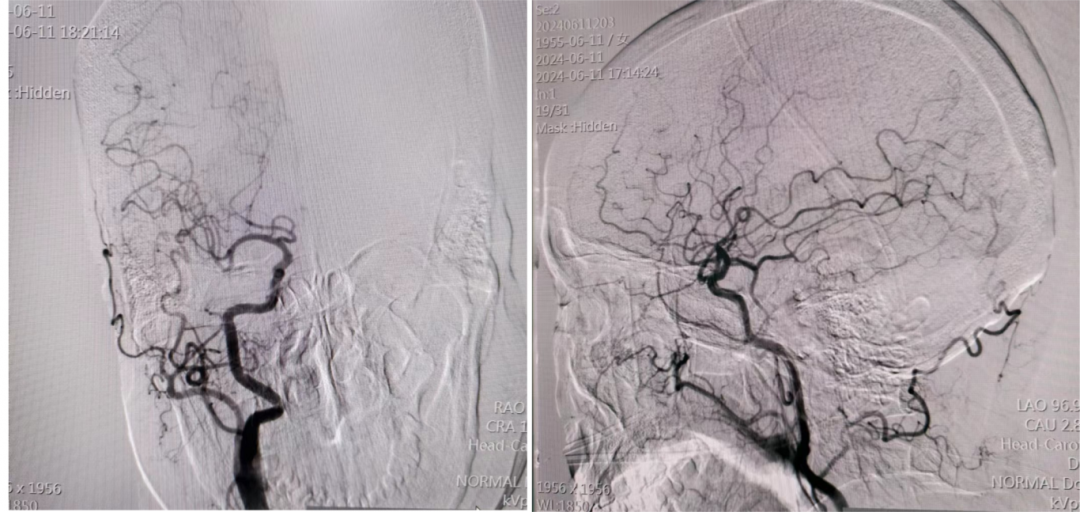

神经内科介入团队接诊后迅速行中间导管负压抽吸完全开通大脑中动脉。

术后1周患者恢复正常,NIHSS评分0分,mRS评分0分。